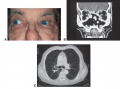

Granulomatosis with Polyangiitis. A) Restrictive strabismus due to inflammatory tissue extending in to medial aspects of orbit. B) Coronal CT scan showing extensive destruction of the nasal and sinus cavities with inflammatory tissue extending into orbits and brain (arrow). C) CT of chest showing cavitary lung lesions (arrow). (courtesy of Jeffrey Nerad, MD - AAO ref (47)).